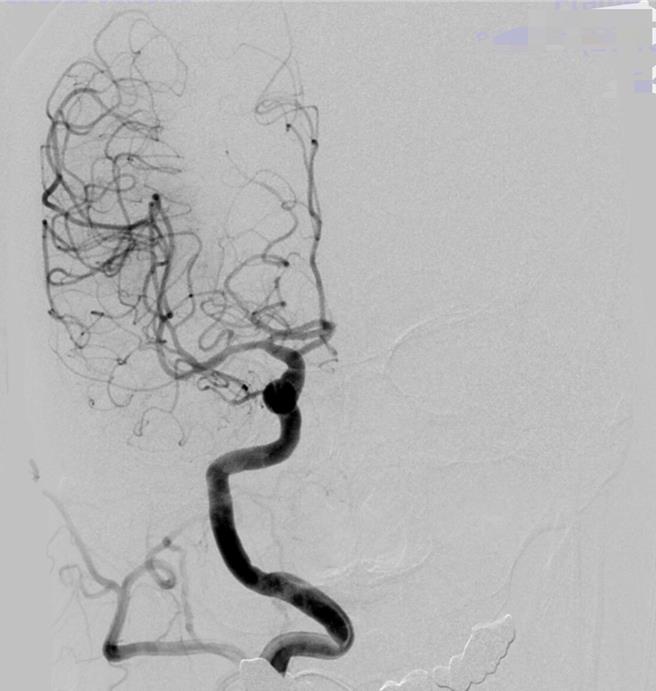

从病患的血管摄影可看出,右半边后面的血管都不见了,即血栓塞住,血流过不去。(光田医院提供)

神经放射治疗科副院长严宝胜指出,治疗时进行动脉取栓评估,会用医疗AI智慧仪器设备去侦测哪一条血管堵住,仪器会侦测出血栓确切位置,再使用器械进入血管内把血栓取出。从该病患血管摄影可看出,右半边后面的血管都不见了,也就是血栓塞住血流过不去,影响的范围很大,必须尽快进行颅内动脉取栓。